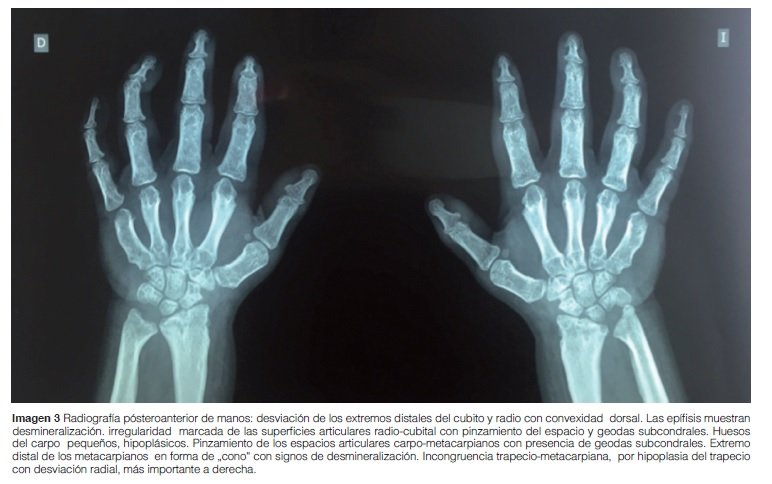

Manos: Desmineralización difusa, extremo distal de metacarpos en forma de cono, huesos del carpo hipoplásicos, pinzamiento y geodas subcondrales en espacios articulares carpo-metacarpianos (Imagen 3).